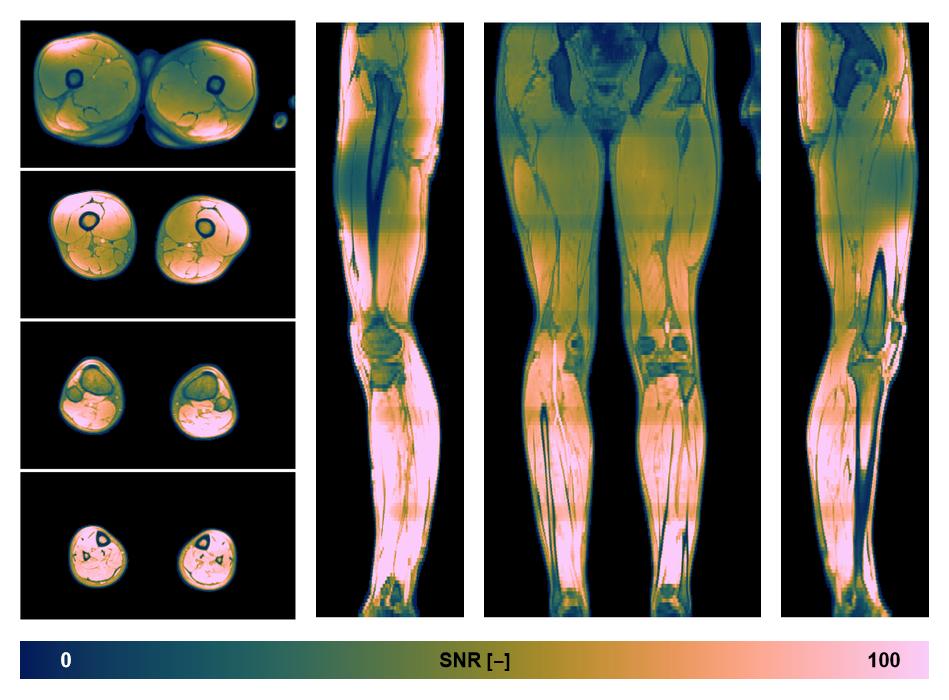

• SNR distribution

The SNR distribution of the dixon data.